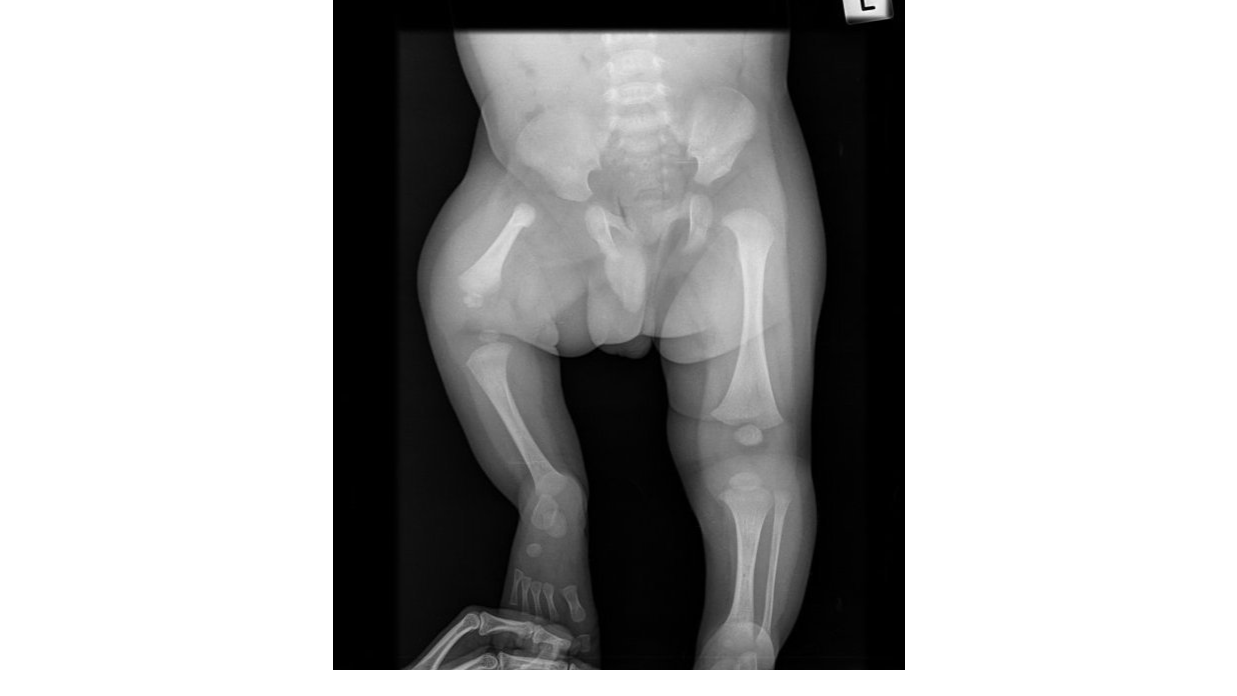

Simple wish for Smiley Riley. My wife and I are starting this campaign to hopefully grant one simple wish for our Grandson Riley. Riley had been a little fighter ever since he was born, his journey was always going to be a long one right from the very start. He was born with PFFD, which stands for Proximal Focal Femoral Deficiency, a short Femur in the upper leg, and Fibular Hemimelia, a missing Fibular in the lower leg. The ankle of his short leg is level with the knee of the other. He also had a fused bone in his head and no soft spots. He needed major Cranio-Facial surgery to correct his forehead. At the age of 5 months he had his forehead re-moulded. This was major surgery. Several months later Riley's father noticed something not quite right with one of Riley's eyes. They took him to the Dr, and sent for scans. This is when they found out that Riley had Retino Blastoma, Eye cancer. He had his eye removed 1 week later, as the cancer was dangerously close to reaching his brain. Riley then had 6 months of Chemotherapy. This was out of the blue and totally unrelated to any of Rileys other problems, and devastated us all. This Chemo has an adverse effect to the other surgeries Riley has received. Late 2016 Riley had the first operation to lengthen his little leg. They fixed a rod to his leg to stretch the bone, which was broken to allow this to happen. He was supposed to get a 7cm increase in length this time and again later down the track. This wasn't to be. The chemo stopped the bone from growing. They managed to get 4 and had to stop. The chemo also stopped any antibiotics from working and he got an infection. He now has to have his leg Amputated. Not only that, he has to have more head surgery because the chemo stopped that bone from growing too. Without the chemo both of these procedures would have worked. Riley's whole family is devastated, to say the least. Although Riley is having trouble coming to terms with the fact that he is losing his leg, it is a lot to take in for a 6 year old, who has been through so much in his short life. Despite all this Riley has not let any of this change his happy friendly nature. He astounds everyone with his enthusiasm, he has a smile for everyone, and has a happy nature that is contagious to everyone he speaks to. He had the Dr."s and his school teachers wrapped around his little finger. This Campaign is to grant Riley his only wish. To go on a plane, and to swim with the dolphins. We would like to send Riley's parents and his 2 younger sisters Kaiesha and Kiara to seaworld to swim with Dolphins and have the break they deserve. Well maybe not Kiara as she is too young, she can stay with Nanna and Poppy. Rileys story can be followed at "the Journey with Smily Riley" facebook page. Thank you for reading this through, and becoming part of his journey.

Riley DennisRiley has been in and out of hospital since he was a baby, Cranio-facial, eye cancer and now a leg amputation, we just wish to send him with his family to Queensland from Adelaide, so Riley can swim with the dolphins. His only wish.